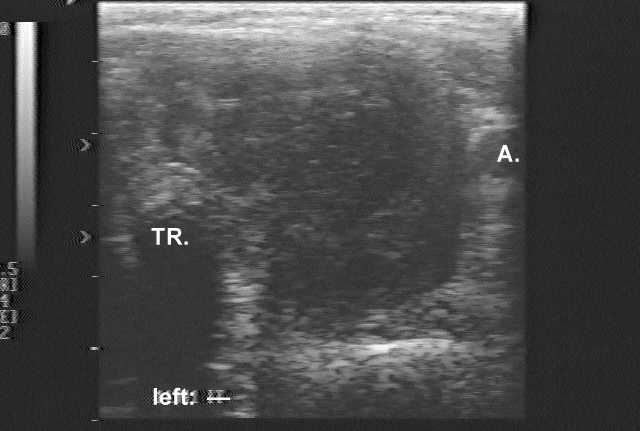

Ultrasonography: demonstrated a greatly enlarged hypoechogenic thyroid spreading retrotracheal and substernal. The vascularization was absent.